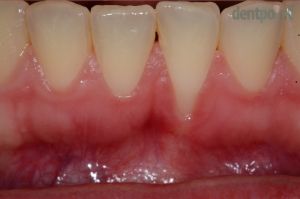

Ínyvisszahúzódás kezelése

Parodontológiai kezeléseink közé tartozik a visszahúzódott fogíny, más néven ínyrecesszió ellátása is. A fogíny a beavatkozást követően tökéletesen egészséges és ismét képes rá, hogy megvédje a fogat az esetleges károsodásoktól vagy a hideg-meleg ételek, italok okozta ingerektől!

Recessziófedés: Dr. Szvoboda Balázs

1) Kiindulási helyzet

2) Ínyrecesszió fedése